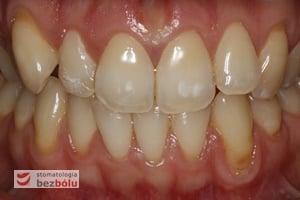

Częstym powodem, dla którego pacjenci zgłaszają się do lekarza dentysty są recesje dziąsłowe. Stanowią one narastający problem zdrowotny ponieważ, poza defektami natury estetycznej, powodują również zwiększenie dolegliwości na bodźce bólowe o charakterze chemicznym (kwaśne, słodkie pokarmy), termicznym (zimno, ciepło) i mechanicznym (wrażliwość na zadrapania, dotknięcia, ukłucia). Skutkiem recesji dziąsłowych jest także zwiększona podatność na próchnicę.

Recesje dziąsłowe mogą mieć różnorakie przyczyny i przybierać wielorakie formy. Oceniając stopień głębokości recesji oraz definiując występowanie czynników etiologicznych podejmuje się decyzję o sposobie leczenia.